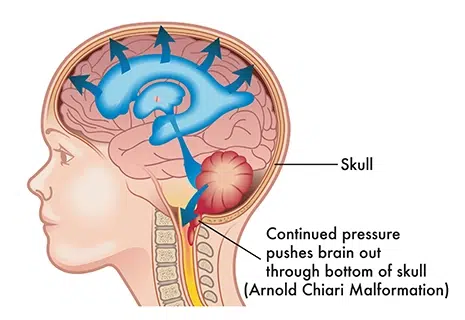

Аномалия Арнольда-Киари: MRI снимки